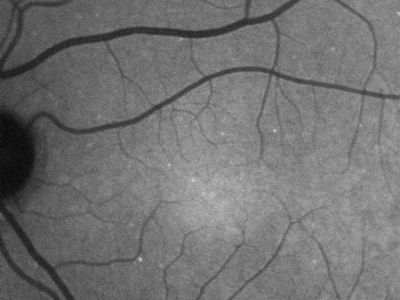

According to researchers, the new technique, called DARC (detection of apoptosing retinal cells), uses a specially-developed fluorescent marker that attaches to cell proteins when injected into a patient. This causes damaged retinal cells to appear as white fluorescent spots during an eye exam.